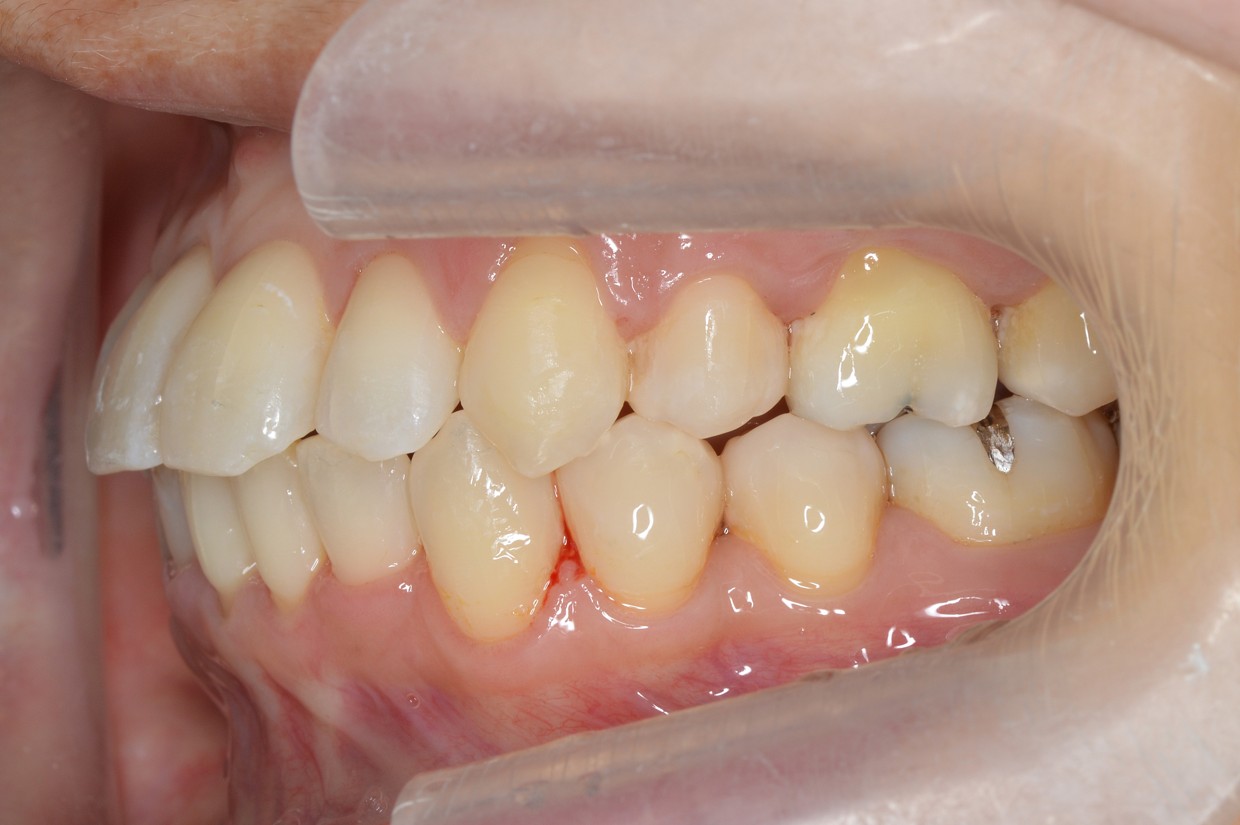

症例1

| 項目 | 詳細 |

|---|---|

| 患者様データ | 30代 女性 |

| 来院時の主訴 | 「上下のガタガタ歯並びと噛み合わせが気になる。」 |

| 矯正法 | 上の歯2本を抜歯しての矯正 |

| 通院期間 | 2年9ヶ月 |

| 治療費 | 総額:1,070,000円(税抜) 【内訳】 精密検査50,000円、メタルワイヤー矯正800,000円、月に1度の調整料5,000円、後戻り防止のリテーナー35,000円×2 |

| リスクと副作用 |

①歯を動かす事による痛みがあります。また、装置に慣れるまでは、口内炎ができやすいです。 ②歯肉が退縮するリスクがあります。装置が全ての歯に付くので、ハミガキが難しくなります。 ③長期的なメインテナンスが必要 |

| ここがこだわりのポイント!☝ |

この患者様の場合、歯並びのガタガタが強かったことや、抜歯したスペースを埋めるのに時間がかりました。ホームケアも大変だったと思いますが、とてもきれいな歯並びに改善することができました。 |